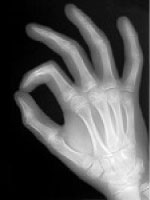

バイ・デジタルO-リングテスト(BDORT)とは、

筋の緊張(トーヌス)を利用して生体情報を感知する検査手技です。

「生体そのものが敏感なセンサーで、身体に害となる物を手に持たせると筋の緊張は低下し、逆に有効な薬剤では緊張が良好に保たれる」という原理に基づいています。